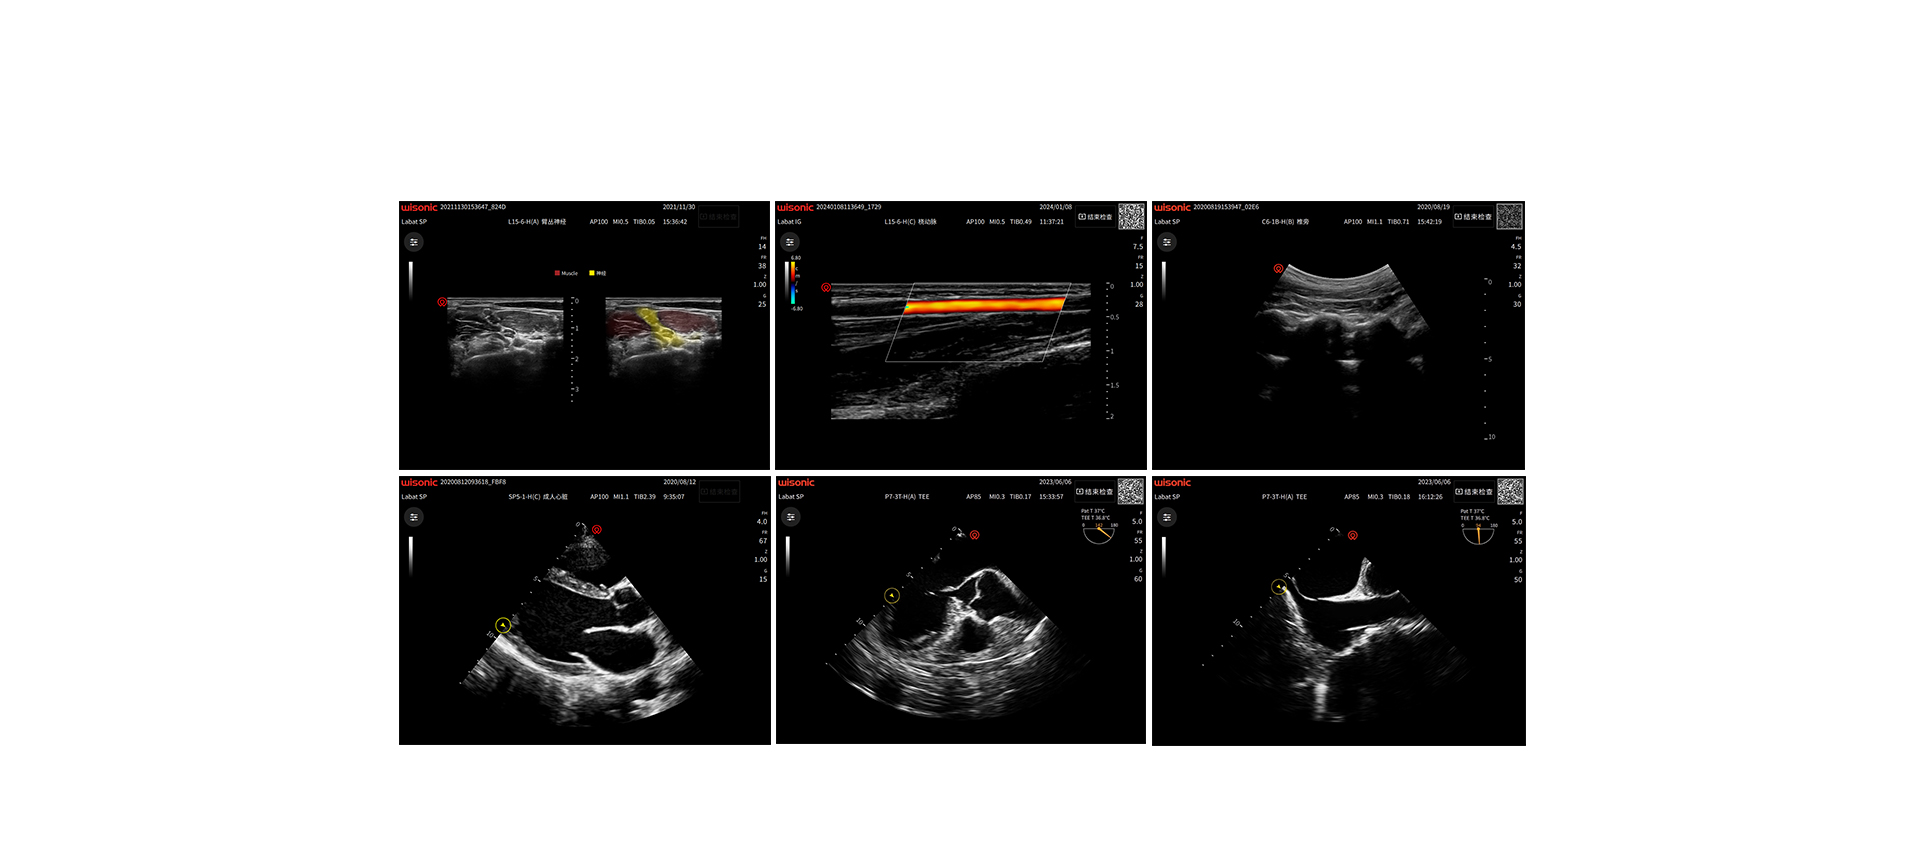

美图鉴赏

临床图片